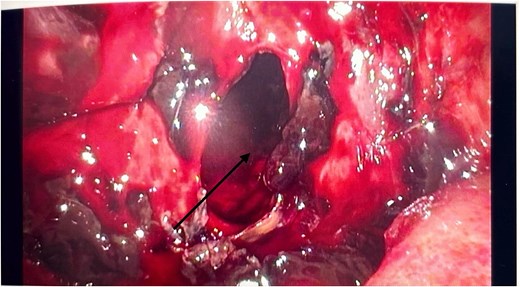

He had an emergency diagnostic laparoscopy. The intraoperative findings included four quadrant haemoperitoneum, ileus involving the stomach, small and large bowels, pelvic floor peritoneal nodules, and a cavity in the retro-colic posterior peritoneum over the pancreas extending into the pancreatic parenchyma with oozing of blood, as shown in Fig. 3.

Intraoperative laparoscopic picture showing a haemorrhagic cavity in the retroperitoneum extending into the pancreas (black arrow).

There were no other obvious signs of peritoneal or omental disease. About 2.6 L of haemoperitoneum with clots was drained during the surgery and the oozing cavity was packed with Surgicel haemostatic gauze, as shown in Fig. 4.

Intraoperative laparoscopic image showing the cavity packed with Surgicel haemostatic gauze (black arrow).